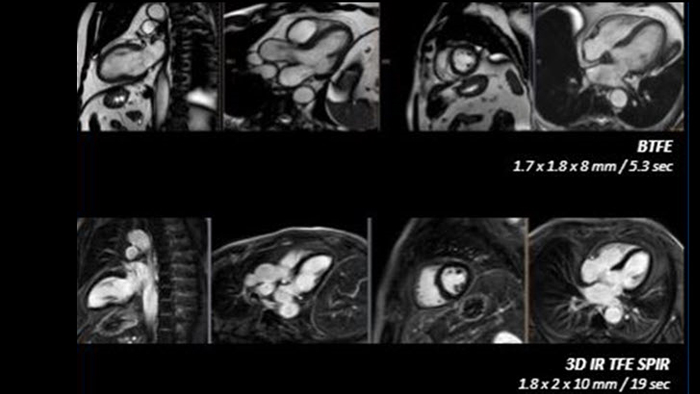

Ingenia Ambition 1.5T

Realize the potential of MR throughout the pathway with ultrafast exams, optimized workflow, high-quality diagnostic imaging and enhanced patient comfort.